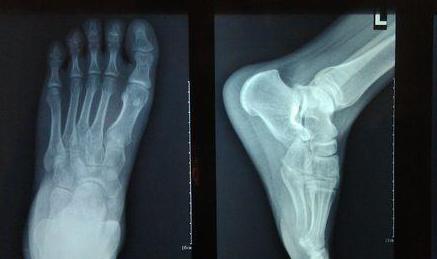

初步处理阶段:迅速叫人拿冰块或者冷水过来冷敷,用冰敷袋放置疼痛处,以降低发炎反应并可有效止痛。(此举的目的是冷却血液,让其凝固,崴脚之后血管肯定破裂,防止其出更多的血),想办法把伤足垫高,促使静脉回流,从而减轻肿胀和疼痛,并且减少受伤部位的活动度和对受伤处副韧带或肌肉的牵拉,以避免损伤的加重。确认没伤到骨头可以自行解决,伤到了还是乖乖去医院吧!!一般情况不会伤及骨头